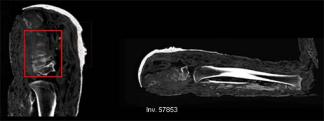

A feltételezett ókori egyiptomi gyerekek múmiáit díszítő vékony lemezek tavalyi restaurálása közben derült ki, hogy az antiknak tűnő aranyborítás valójában 1800-ban készült. Az egyik hatvan centiméter hosszú múmiát azóta meg is röntgenezték. A vizsgálat elárulta, hogy a több rétegnyi kötés alatt egy teljes csontváz helyett egyetlen sípcsont rejlik. Ez is egy felnőtt férfié, aki a középkorban élt.